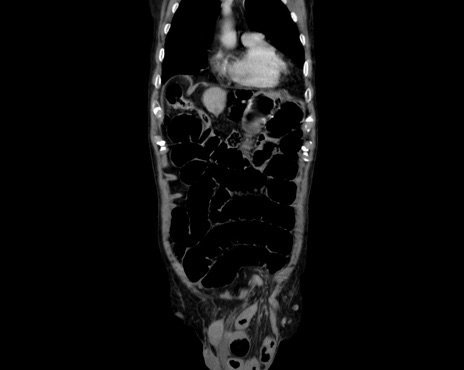

症例26(冠状断像)

【症例】80歳代男性

【主訴】嘔吐

【現病歴】昨晩2回嘔吐あり、今朝になっても嘔吐あり。来院。

【既往歴】胃潰瘍

【身体所見】意識清明、BT 37.6℃、BP 166/95mmHg、HR 100bpm、SpO2 97%、腹部:平坦・軟、腸蠕動音聴取良好、圧痛なし。

【データ】WBC 21900、CRP 1.4